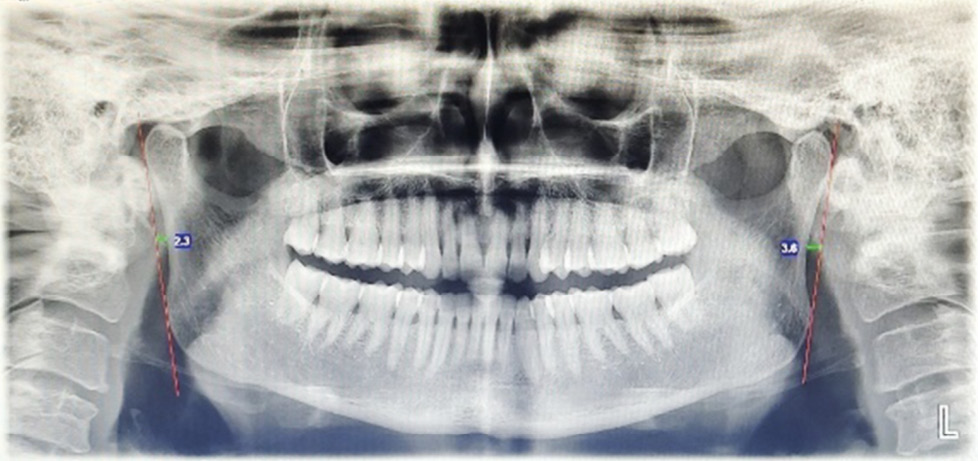

- Gonial angle (GA):

Fig. 1. Bilateral angular measurement of the gonial angle.

It is formed by drawing a line between two imaginary lines that extend from lower border of the mandible to ramus of the mandible.